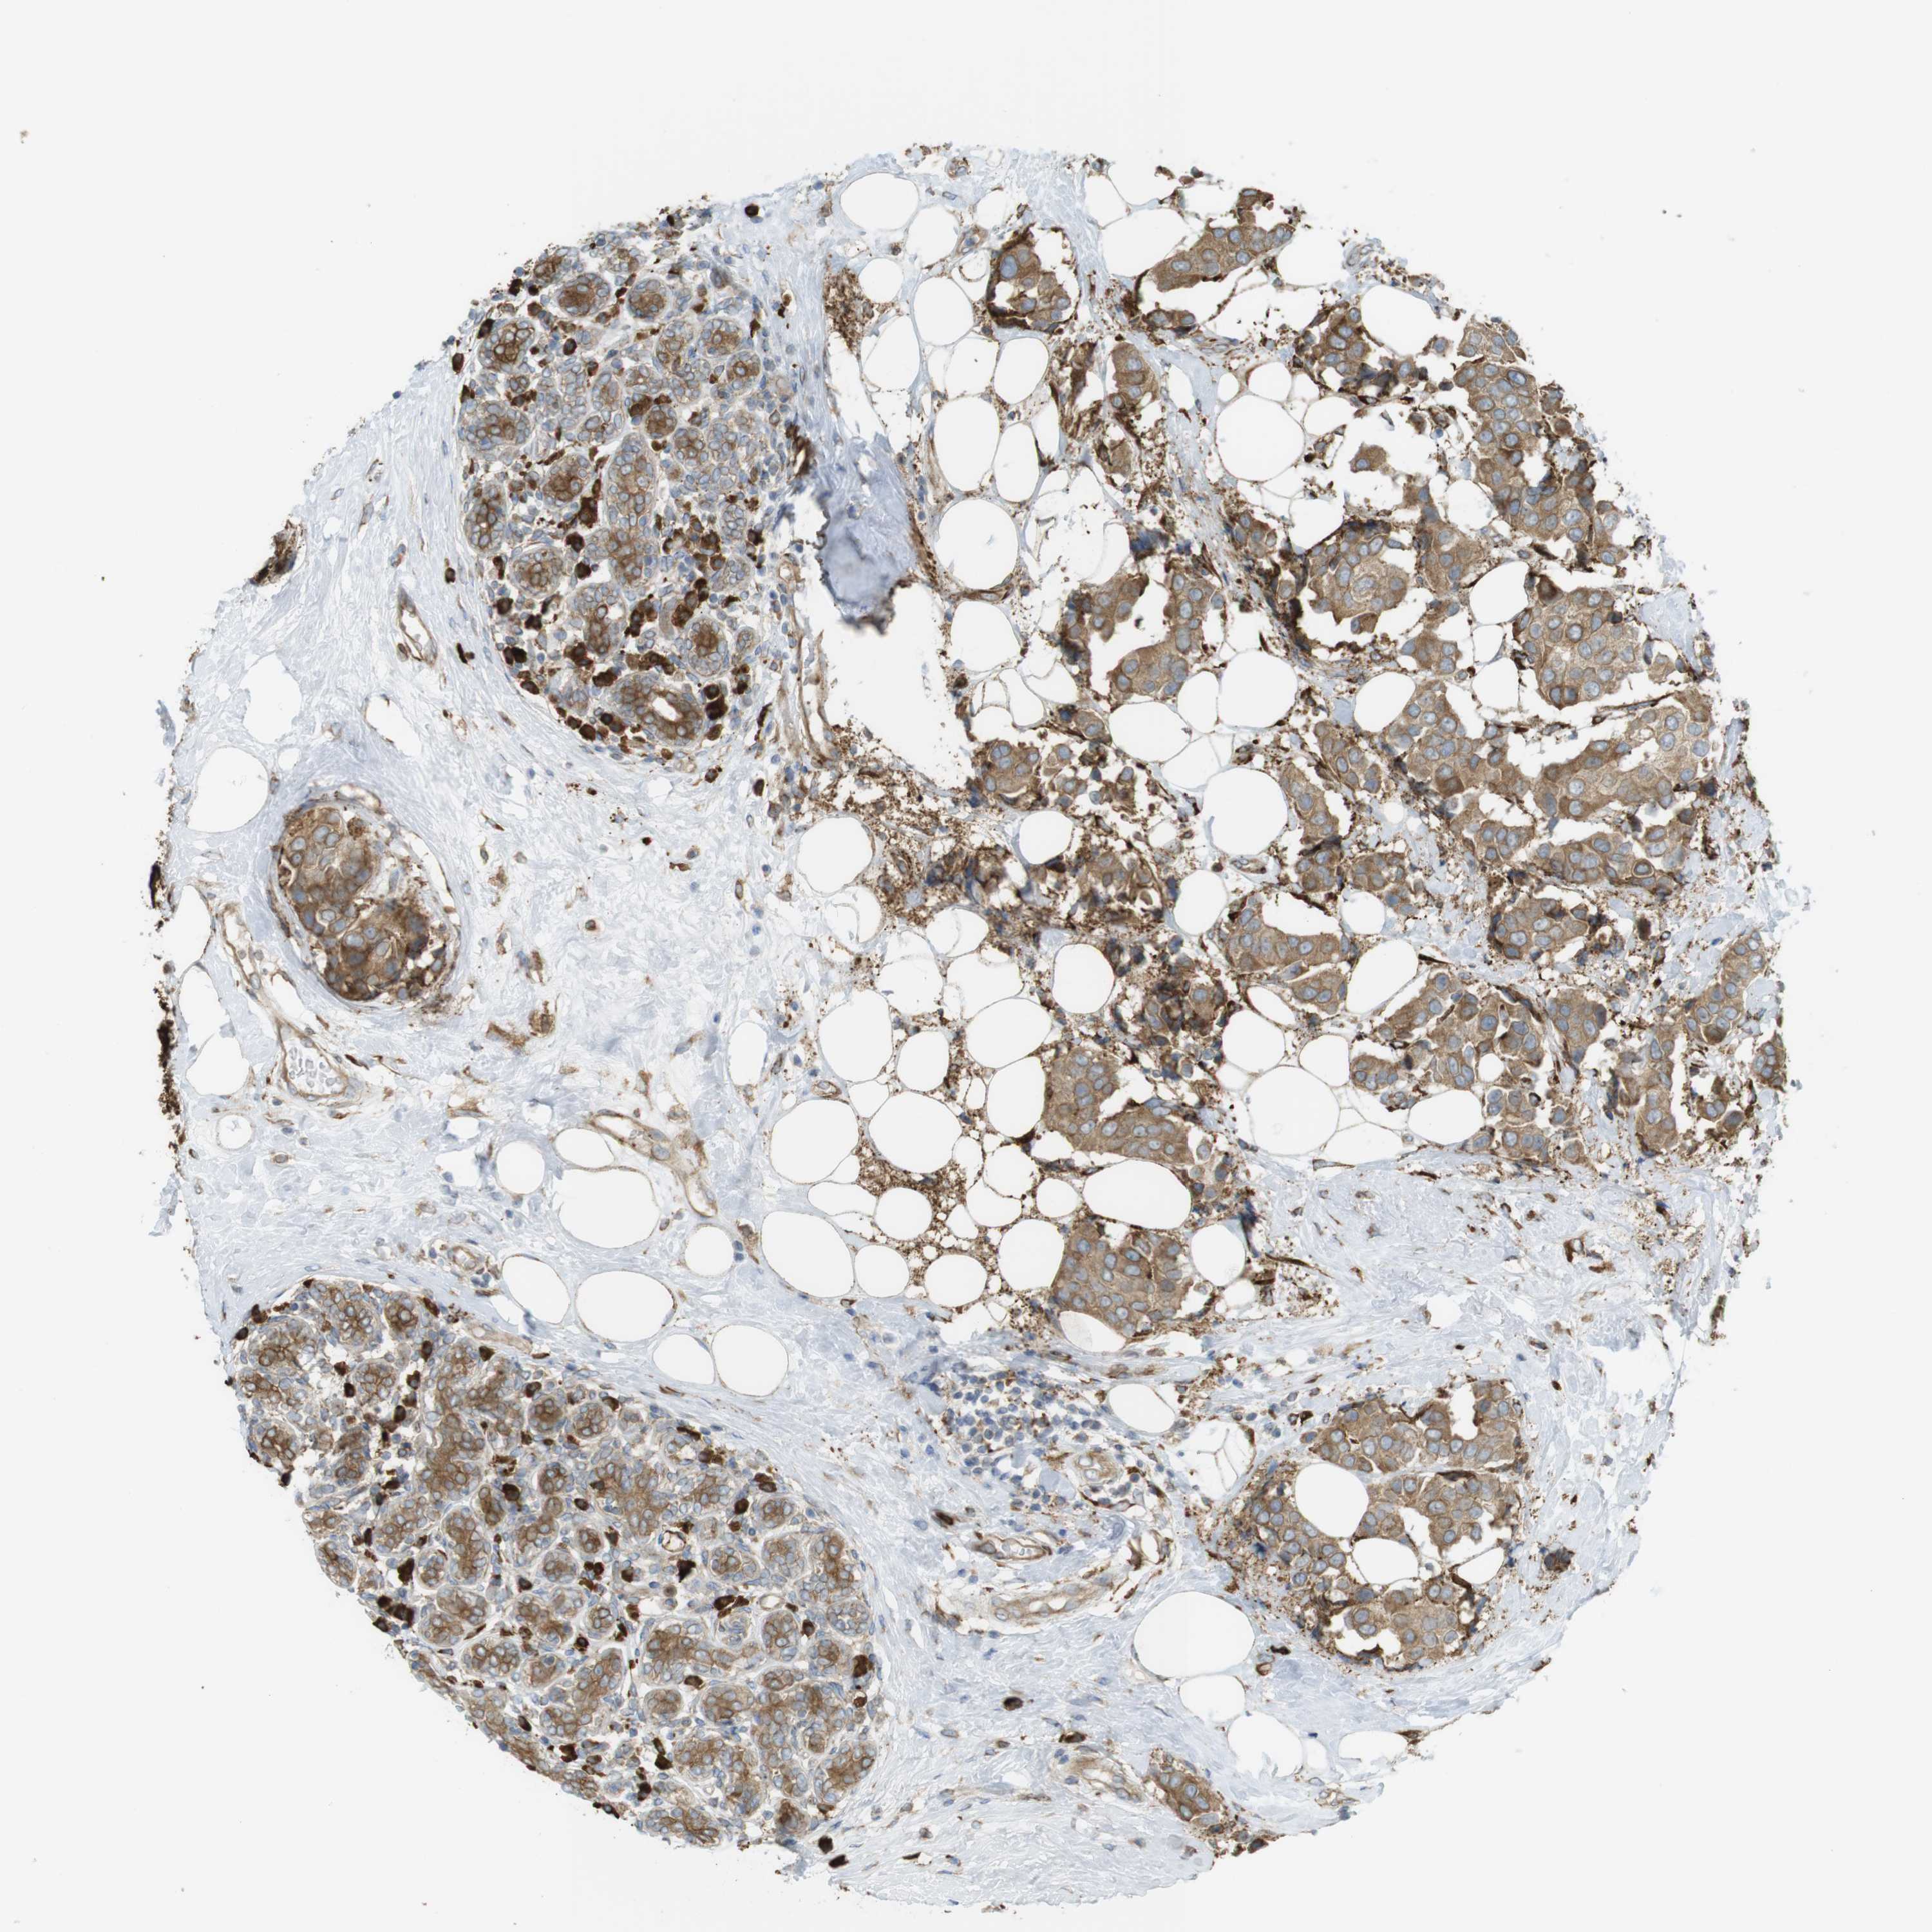

BRCA TCGA BRCA VALIDATION PROTEIN EXPRESSION

ANTIBODIES

AND

VALIDATION